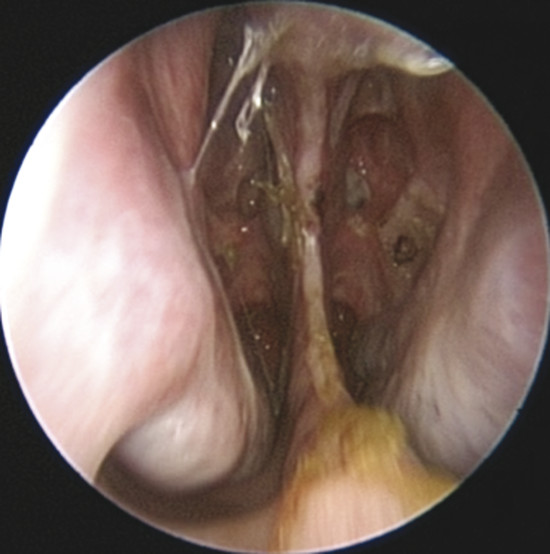

Upon physical examination of the nose, a full diagnosis cannot be made until all crusts have been removed and decongestion of the turbinates has taken place, making it possible to visualize the entire nasal septum. The nasal endoscopy allows appreciating the configuration of the NSP, the presence or absence of adherent crusts on the edges of the defect (Fig. 6‑1), any easily bleeding areas (Fig. 6‑2), and the state of the remaining mucosa, which may present some aspects regarding ischemic conditions (cocaine abuse) (Fig. 6‑3).

If the defect is not circular, but oval in shape (Fig. 6‑5), it is appropriate to obtain an exact measurement of the major diameters: anteroposterior and craniocaudal, vital in choosing the most appropriate surgical technique. The vertical height of a perforation has been predicted to play a more important role in determining the surgical success than the horizontal length because the main tension between the floor of the nose and the dorsum was critical. 2 The final aspect that must be considered for surgery is the location: anterior, posterior, near the floor, or in the cranial part of the septum. Septal spurs must be identified during endoscopic examination. These should be removed during flap harvesting to get one more large and flexible mucosal layer. (Fig. 6‑6). The septum should be palpated with a sticker or with a cotton tip to discern persistent cartilage between mucosal flaps and determine whether cartilage extends close to the edges of the NSP. 2 In perforations that have occurred after septoplasty, there is usually very little cartilage left, and this makes dissection of the flaps more difficult. In this phase it is also important to check the quality of other intranasal anatomical structures, which represented potential donor sites of grafts or flaps, such as the inferior turbinate, the middle turbinate or the floor of the nasal fossa.